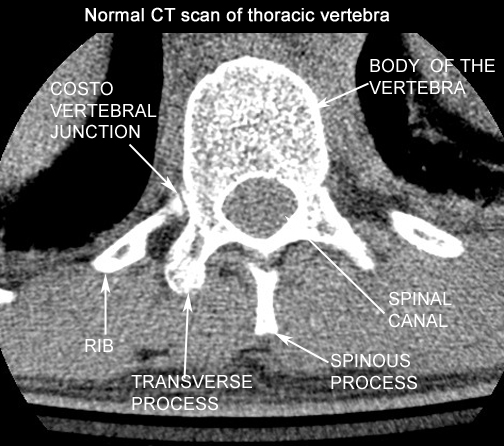

Identify the structures seen. Click the image for labeling.